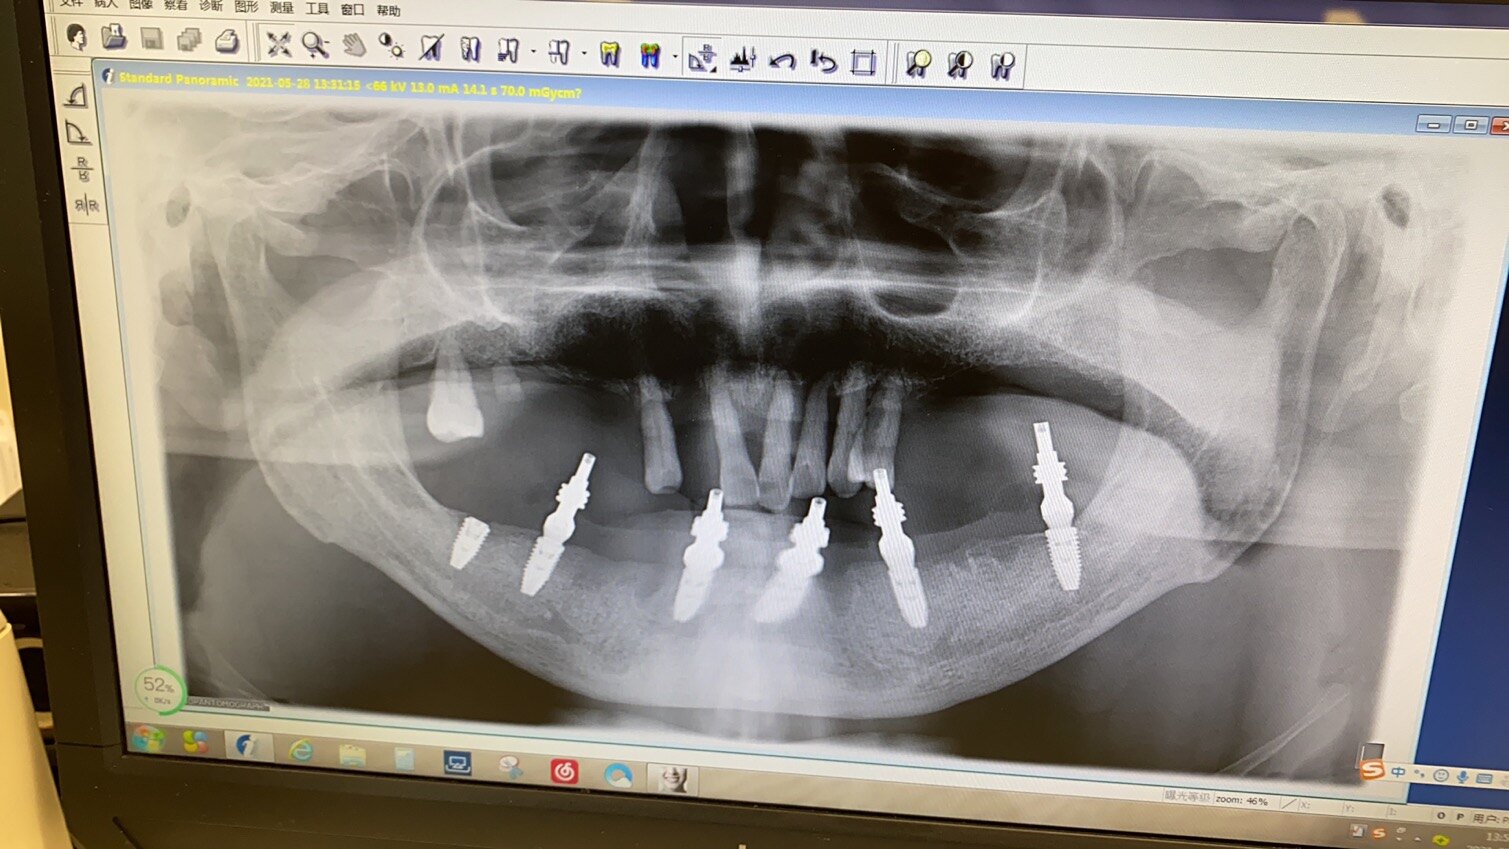

术前阶段。还要进行牙槽骨的CBCT影像检测,检测牙槽骨的高度、厚度、密度。需要进行背部的检测,排除有无放疗的禁忌症。假如手臂和局部的条件都符合上颚栽培,可以进行第二阶段放疗阶段。

去除医生成本,植牙放疗对设备的要求只是特别高的,CT设备、X光等都须要不少费用,先进的设备在检测病人牙槽骨高度密度等项目时会更精准有利。